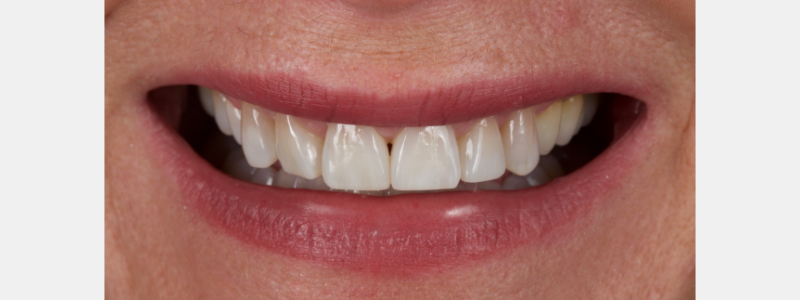

The anterior teeth had lost around 25% of the coronal structure, and dentin was exposed (Figs. 1–3). The patient requested a minimally invasive solution.

After deprogramming with a splint and occlusal equilibration, the anterior teeth were restored with direct composite resin using a minimal prep approach (Figs. 4 and 5). The occlusal scheme was idealized (Fig. 6).